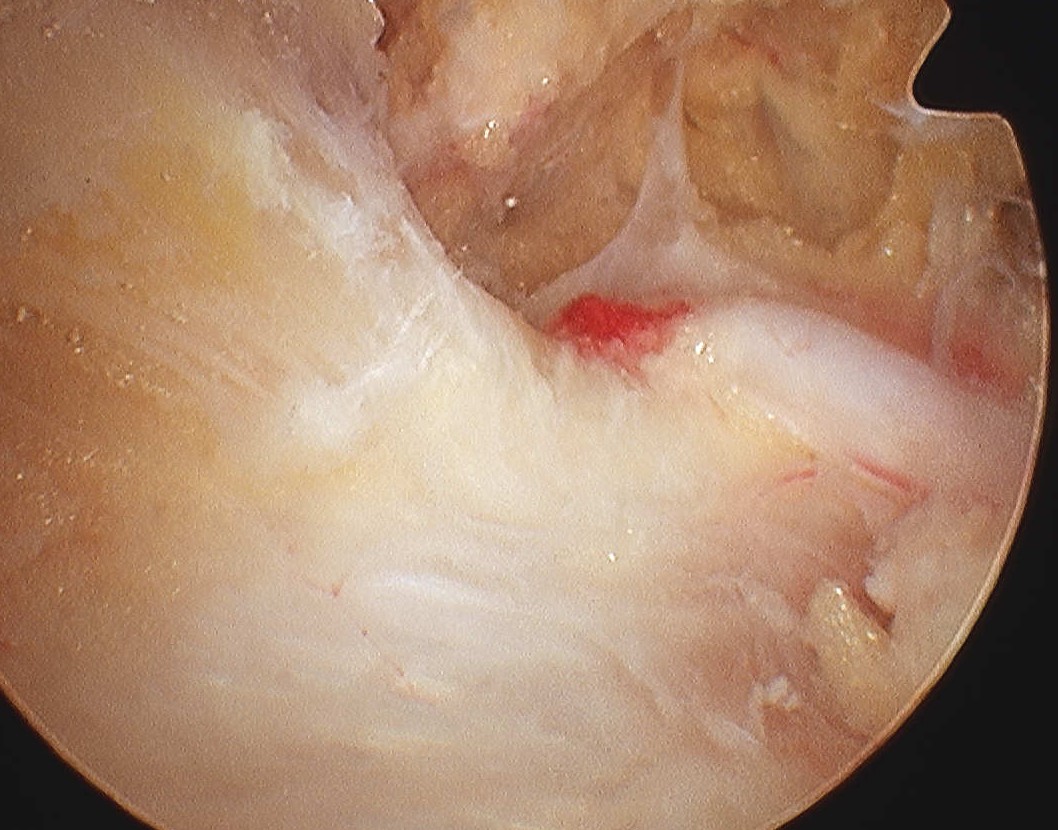

Posterior glenohumeral capsulotomy and cyst decompression

Subacromial space approach